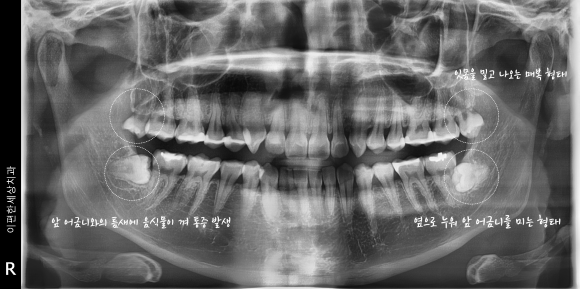

촬영일 : 231124

특히 예시 사진처럼 까다로운 사랑니가 많은 경우에는

입을 크게 벌리는 행위가 많아지고

턱이 눌리는 느낌이 조금 더 심해질 수 있죠.